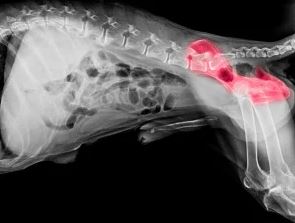

Elle se produit au niveau de l’articulation et se manifeste par une asymétrie de la tête du fémur avec la cavité de l’os du bassin qui doit normalement l’accueillir.

La lecture consiste à apprécier la forme des têtes fémorales, l’enserrement de cette même tête par l’acétabulum, la congruence (rapport entre les surfaces articulaires) de l’articulation, repérer les éventuels signes visibles d’arthrose (ostéophytes,…), et la laxité de l’articulation, mesurée principalement par l’angle de Norberg Olsson.